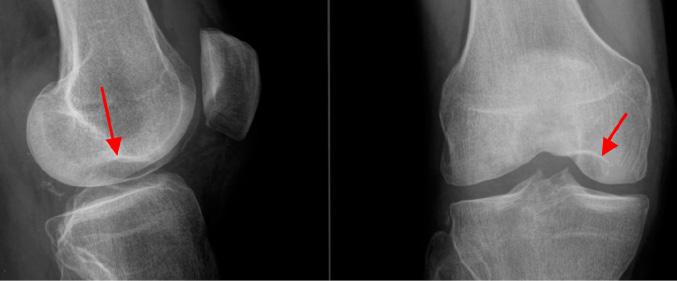

Ostéonécrose spontanée du condyle interne